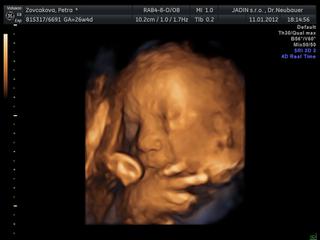

nechodim tu casto, takze nestiham to vsetko sledovat. Urcite mi kopa veci usla, chcela by som sa spytat, kde v Ba robia 4D, kedze vy uz svoje krasne obrazky mate a za kolko. Na nete som sa akosi k cene nedopatrala. Viem len tolko, ze na 4D je teraz ten najvhodnejsi cas. Dakujem